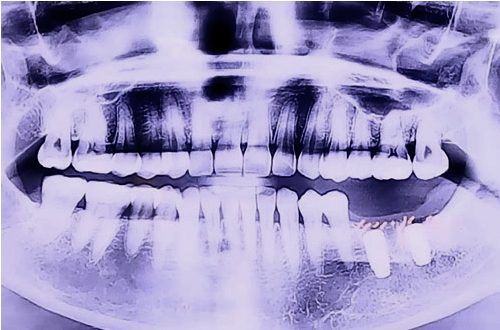

AFTER

문제가 되는 어금니 2개를 발치 후, 잇몸의 염증이 나아질때까지 기다리며 관리를 도와드렸고, 염증이 모두 없어진 것을 확인한 후 뼈이식과 함께 임플란트 수술을 진행하였습니다.

현재 임플란트 후 아직 실을 제거하시기 전이신데, 앞으로 치아를 대신할 보철이 완성되고 나면 다시금 진료일지를 통해 소식 알려드리도록 하겠습니다. ^^